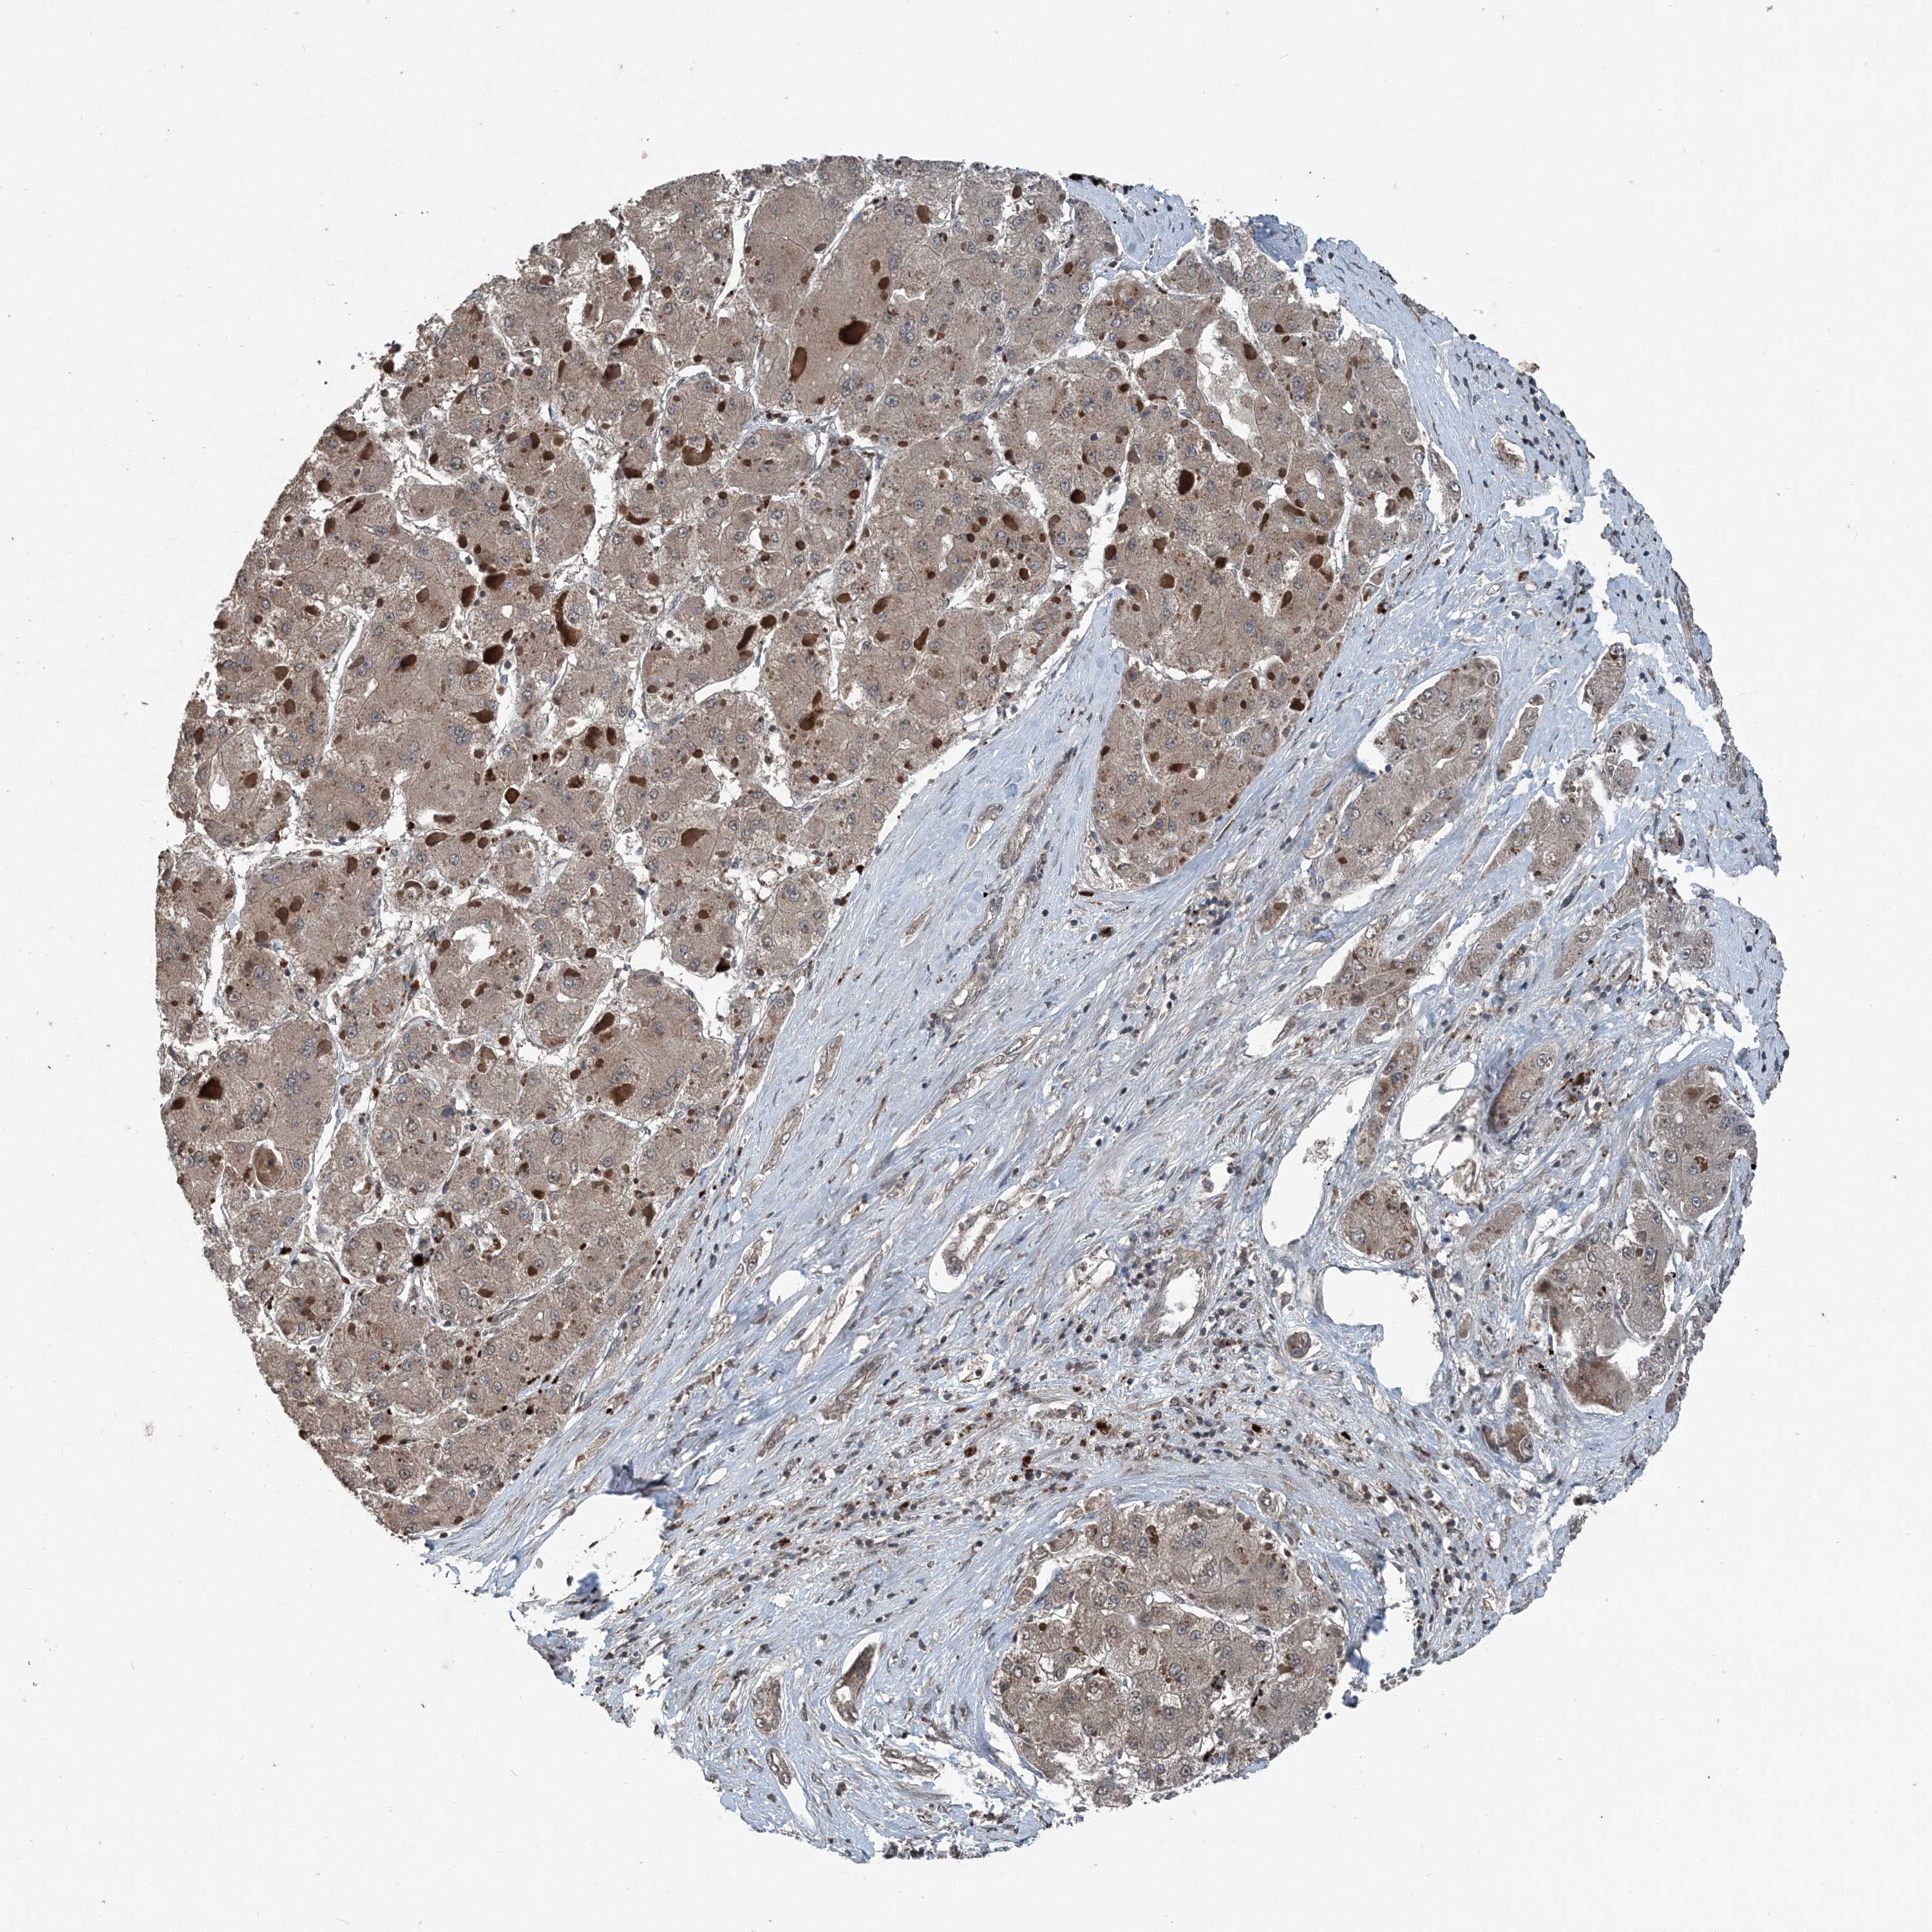

LIVER CANCER - Protein expressioni

A mouse-over function shows sample information and annotation data. Click on an image to view it in a full screen mode. Samples can be filtered based on level of antibody staining by selecting one or several of the following categories: high, medium, low and not detected. The assay and annotation is described here.

Note that samples used for immunohistochemistry by the Human Protein Atlas do not correspond to samples in the TCGA dataset.

Antibody stainingi

Antibody staining in the annotated cell types in the current human tissue is reported as not detected, low, medium, or high, based on conventional immunohistochemistry profiling in selected tissues. This score is based on the combination of the staining intensity and fraction of stained cells.

Each image is clickable and will lead to virtual microscopy that enables deeper exploration of all samples and also displays staining intensity scores, fraction scores and subcellular localization as well as patient and tissue information for each sample.

Antibody HPA053761

Cholangiocarcinoma

Carcinoma, Hepatocellular, NOS